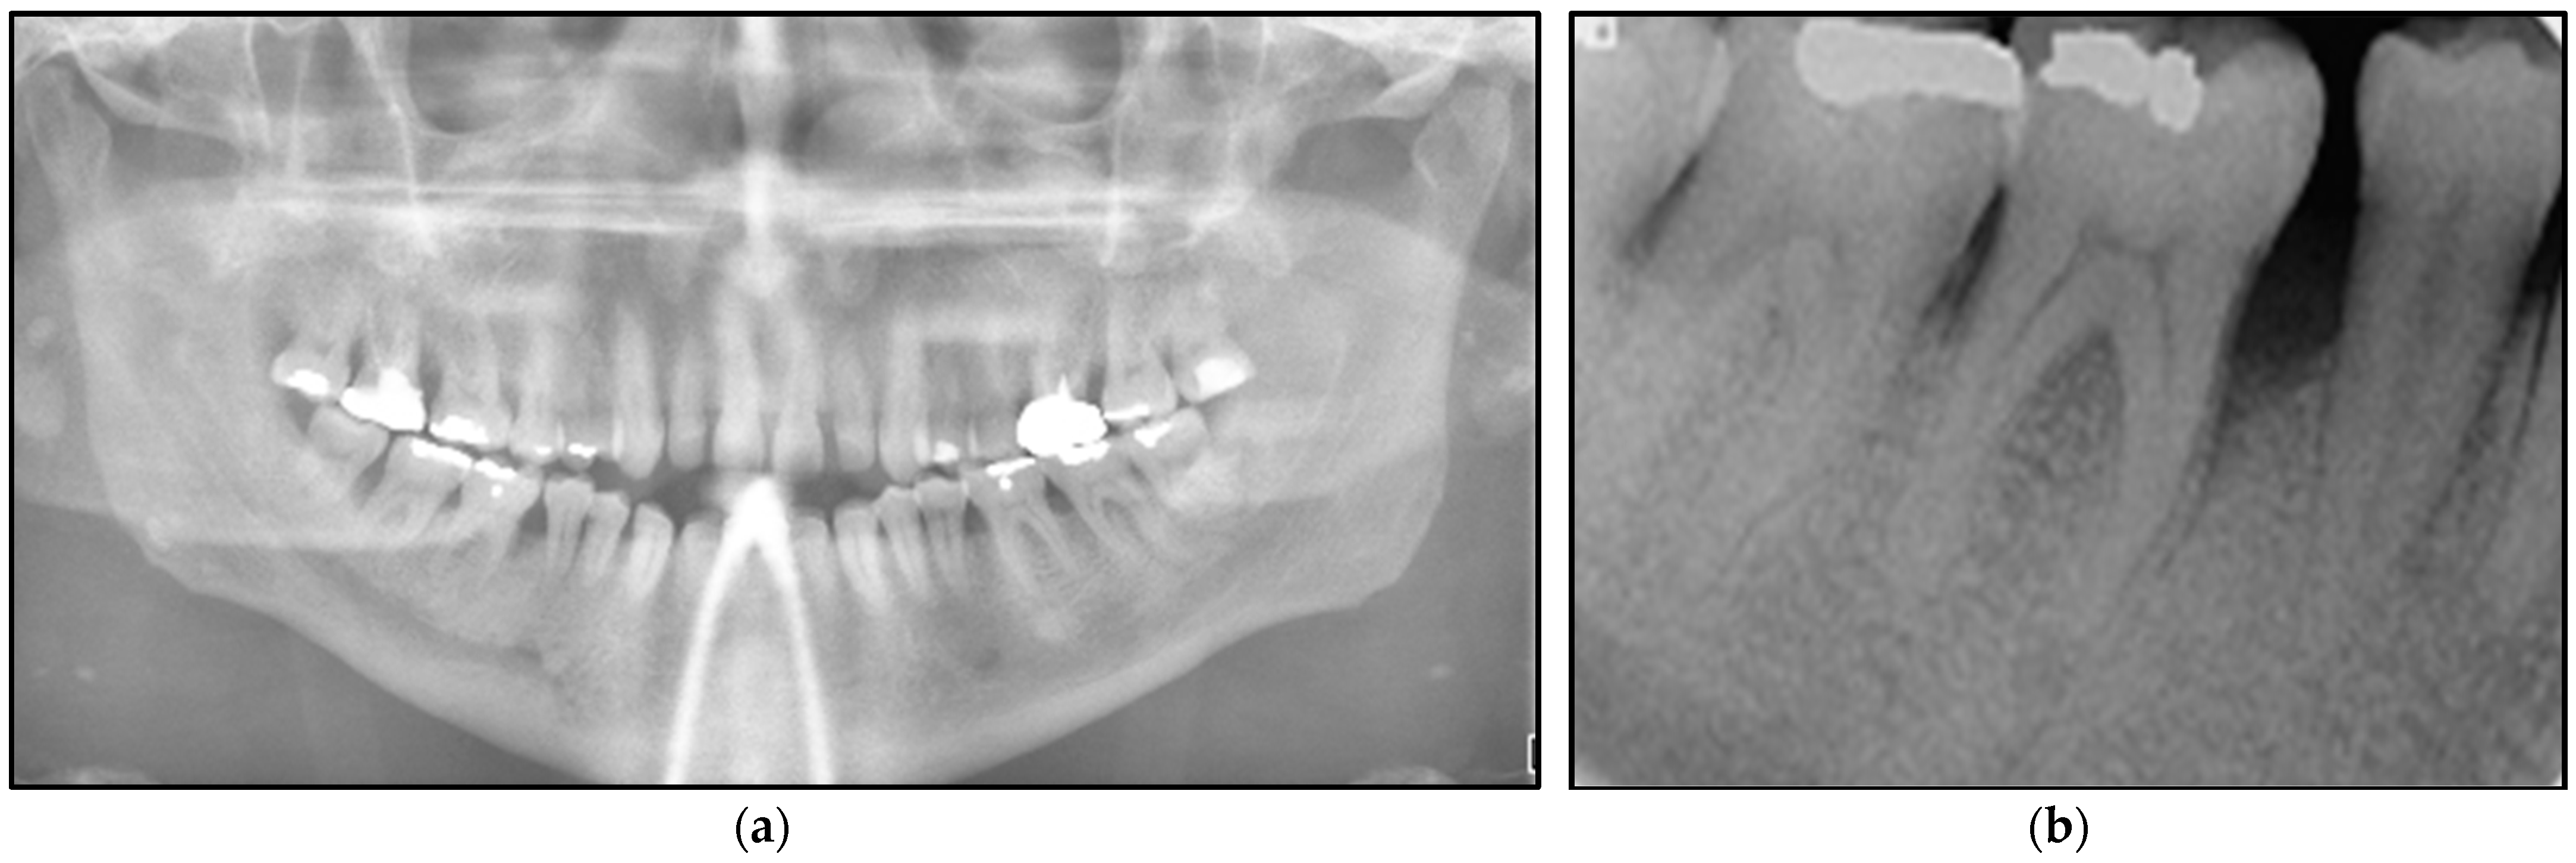

Orthopantomogram (Figure 3a) and long-cone periapical views (Figure 3b) showed an evidence of a localised vertical bone loss involved LR5 distally and LR6 mesially, whereas the rest of the bone levels were within the normal range. It was indicative that the extensive of the lesion led to alveolar loss.

Figure 3. Shows the radiographic investigations. (a) represents the orthopantomogram imaging (extraoral) was taken in order to determine and evaluate the level of bone loss in the area of lower right 2nd premolar (LR5) and 1st molar (LR6) where the intraoral lesions presented compared with the contralateral side. It shows generalised bone loss without involving the bifurcation among the lower molars. (b) represents along-cone intraoral periapical view showing vertical bone loss distal to the LR5 and mesial to the LR6, whereby the intraoral lesion was presented intraorally. The evidence of bone loss is an indicative of the extension of the lesion beyond the soft tissue reaching the periosteum and alveolar bone. Otherwise, both images show no pathology.